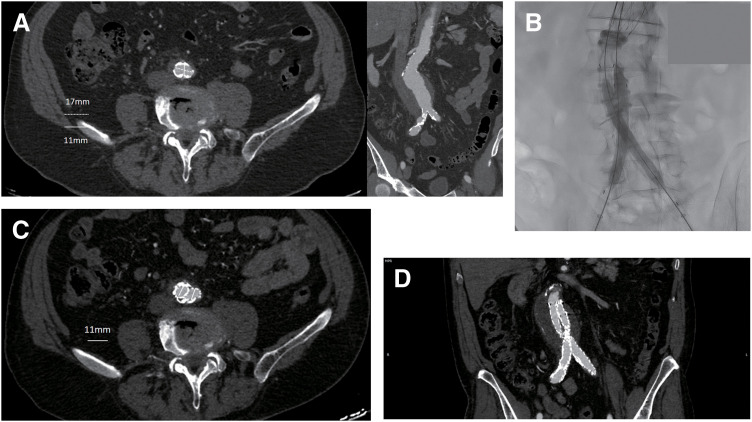

Objectives: A narrow aortic bifurcation poses technical challenges during endovascular aneurysm repair (EVAR). We aim to compare the unibody AFX2 (Endologix, Irvine, CA, USA) vs the bifurcated ALTO (Endologix) system in EVAR patients with a narrow bifurcation. Methods: Retrospective single-center study, including patients undergoing standard EVAR over 3 years. Patients with a bifurcation diameter <20 mm were identified, and outcomes were compared between the AFX2 and ALTO groups. Primary endpoints were primary and overall technical success, primary and overall clinical success, rate of adverse limb events, rate of limb occlusion, and need for secondary interventions. The analysis was repeated using a diameter threshold of <18 mm. Results: Among 151 cases, 26 presented with bifurcations <20 mm and 12 with <18 mm. In the primary analysis, 15 patients were treated with the AFX2 and 11 with the ALTO endograft. Both groups achieved 100% technical and clinical success. No limb occlusions occurred, and no reinterventions were recorded. Preoperative anatomy was suitable for ALTO in all cases, while eligibility for AFX2 was 15 out of 26 cases. Secondary analysis displayed similar results. Conclusions: In patients with narrow aortic bifurcation, the AFX2 endograft can be safely used when appropriate anatomic conditions are met. If the AFX2 system is unsuitable due to other anatomic restrictions, the ALTO endograft is a viable alternative.